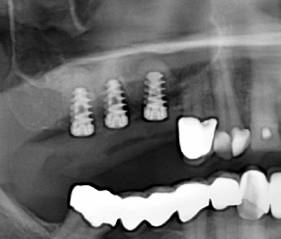

Nach ca. 6 Monaten ist der implantierte

Rinderknochen um die Implantate zu eigenem

sehr kompaktem Knochen umgebaut worden,

das viel fester ist, als der eigene Kieferknochen

des Oberkiefers. So wird der Knochen stark mit dem Knochenersatzmaterial verdichtet so das

Implantate mit ihrem groben Gewinde sehr gut im Knochen verankertwerden.